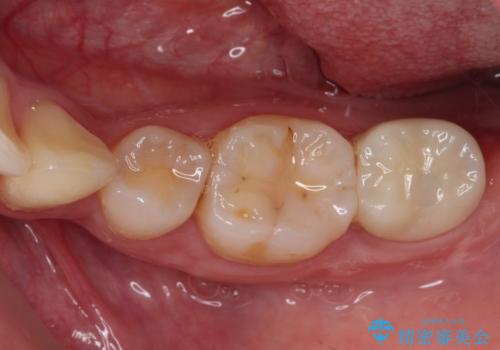

放置した虫歯 根管治療とオールセラミッククラウン

- 奥歯の虫歯を放置してしまい、痛みを感じることがあるとのことで来院された患者様です。

術前の診査では、神経を取り除かなくても済む可能性が示唆されましたが、実際に虫歯除去を進めたところ、レントゲン写真から読み取れる通り、神経組織にまで虫歯が及んでいることが分かりました。

速やかにラバーダム下にて根管治療を行うこととし、その後オールセラミッククラウンにて補綴治療を行うこととしました。